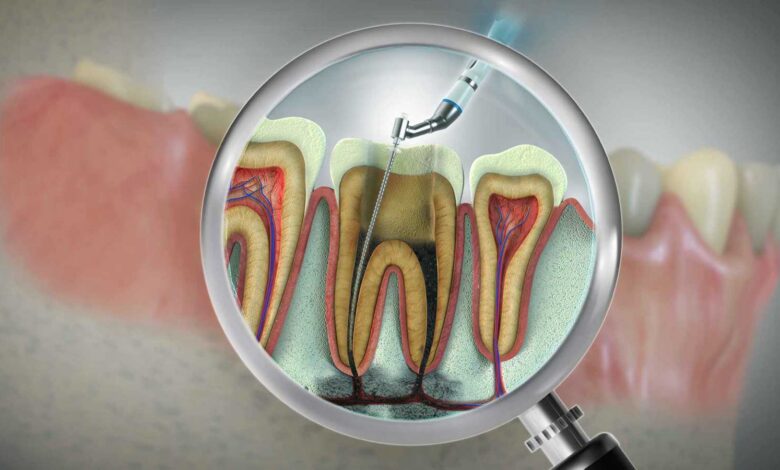

رغم أن معظم الأفراد لا يحبون إجراء علاج قناة الجذر (علاج العصب)، تشير دراسة جديدة إلى أن هذا الإجراء الشائع قد يقدم فوائد تتجاوز صحة الفم. إذ يمكن أن يحسن مؤشرات القلب والأيض ويقلل من خطر الإصابة بأمراض القلب والسكري من النوع الثاني.

ووفقا لـ”واشنطن بوست” فإن الدراسة، التي نُشرت في مجلة الطب الانتقالي، تابعت 65 مريضًا في معهد طب الأسنان بمستشفى جايز في لندن. خضعوا لعلاج قناة الجذر أو جراحة ما بعد الجذر لإزالة العدوى والالتهاب من الأسنان المصابة. وجمع الباحثون عينات دم في خمس فترات: قبل العلاج، وبعد ثلاثة أشهر، وستة أشهر، وسنة، وسنتين.

وبعد العلاج، تحسنت هذه المؤشرات بشكل ملحوظ، مع انخفاض مستويات الكوليسترول والأحماض الدهنية خلال ثلاثة إلى ستة أشهر. وبحلول نهاية متابعة السنتين. أظهر معظم المرضى تحسنًا واضحًا في مستويات السكر والكوليسترول ومؤشرات الالتهاب.

وقالت الباحثة الرئيسة صادية نيازي، محاضرة كبيرة في كلية كينغز لندن: “وجود التهاب حول قمة الجذر يمكن أن يزيد من خطر الإصابة بالسكري. وأمراض القلب وحالات صحية جهازية أخرى. العلاج الناجح يعزز الشفاء ويحسن الصحة العامة والرفاهية”.

وعلى الرغم من أن الدراسة لم تتضمن مجموعة ضابطة، وقد تكون بعض التحسينات نتيجة لتغييرات في نمط الحياة، إلا أن النتائج تبرز التأثير الصحي الأوسع للعناية بالأسنان. وأكدت نيازي: “علاج قناة الجذر ليس مجرد إنقاذ للسن، بل يمكن أن يؤثر إيجابيًا على الصحة العامة”.